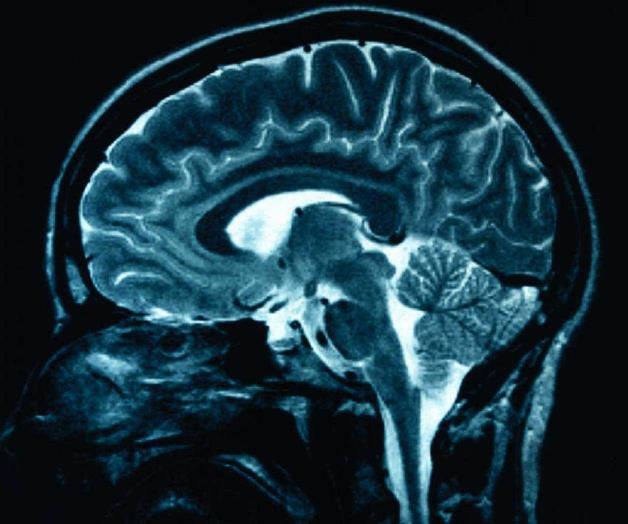

Los investigadores de la empresa Neurobotics y el laboratorio de neurorrobótica del Instituto de Física y Tecnología de Moscú (MIPT, por sus siglas en inglés), lograron reconstruir las imágenes que está viendo una persona mediante el análisis de la actividad eléctrica del cerebro.

Los científicos seleccionaron aleatoriamente cinco vídeos de YouTube de diferentes categorías: abstracción, cascadas, rostros humanos y velocidad. Les enseñaban los vídeos a las personas y, al mismo tiempo, se realizaba una electroencefalografía.

Se logró demostrar que la frecuencia de las ondas del electroencefalograma para diferentes categorías de vídeos es diferente. Esto hizo posible analizar la respuesta del cerebro a los vídeos en tiempo real.

Luego, se seleccionaron al azar tres categorías de los vídeos mencionados y dos redes neuronales, desarrolladas por científicos, reprodujeron imágenes que estaban viendo los participantes de la prueba. Las redes neuronales crearon unas imágenes realistas y en el 90% de los casos resultó posible determinar la categoría del vídeo.